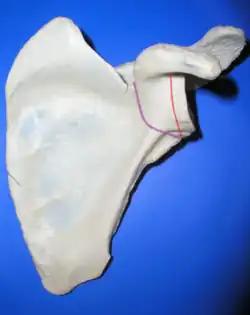

Anatomic neck: red, Surgical neck: purple

Anatomic neck: red, Surgical neck: purple -